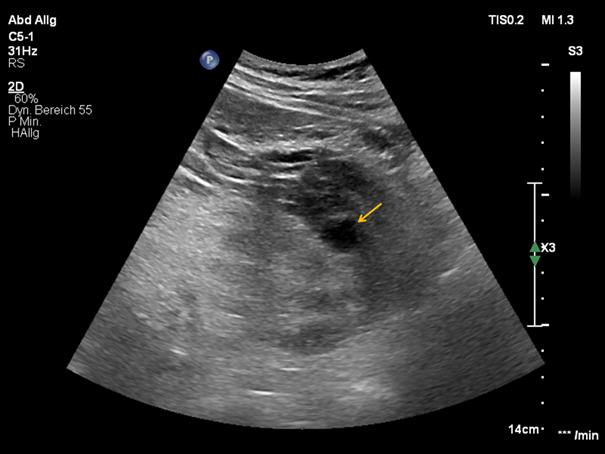

CEUS depicted contrast-filling of a pseudoaneurysm in the lower pole of the left kidney measuring 22 x 13 mm, additional CEUS detected the feeding vessel of the pseudoaneurysm. A pararenal hematoma was also demarcated. (Figure 3)

Figure 3 Side by side mode with contrast-enhanced ultrasound (a) and B-mode (b); Demonstration of RAP (arrow) and the feeding vessel.